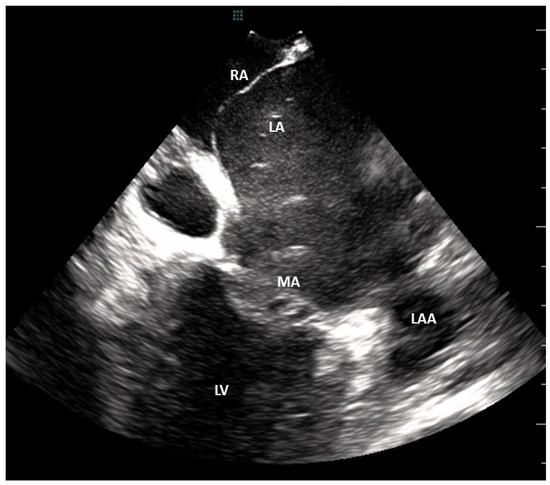

Cardiac Tomography and Cardiac Magnetic Resonance to Predict the Absence of Intracardiac Thrombus in Anticoagulated Patients Undergoing Atrial Fibrillation Ablation

2. Methods

2.2. Imaging Protocols